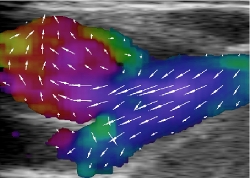

Danish researchers build world's most powerful ultrasound scanner